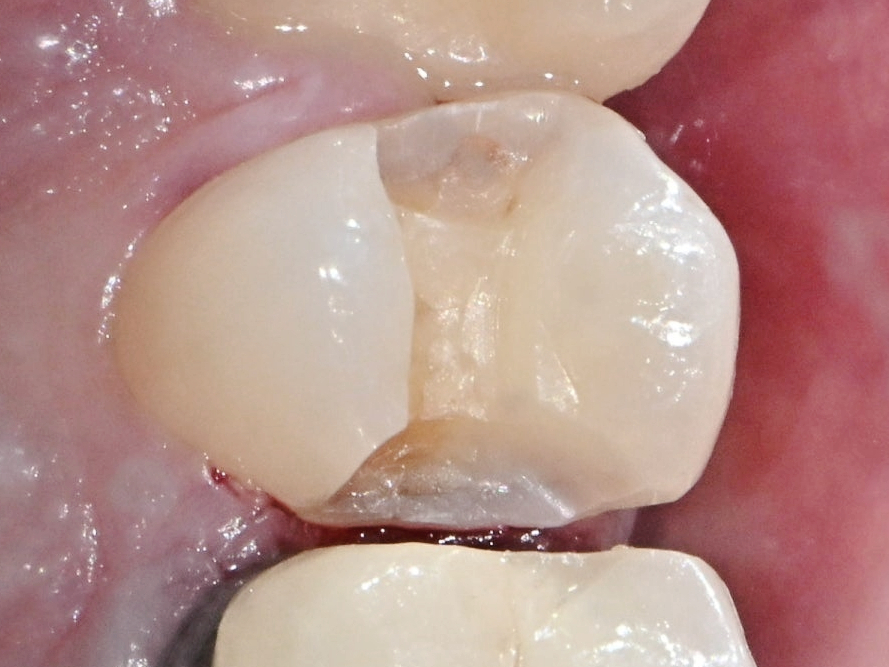

2단계. 충치 제거 & 이빨 모양 성형

마곡동치과_충치 삭제

본격적인 치료는 충치를 깨끗하게 제거하는 것부터 시작됩니다.

마취 후, 썩은 부위를 삭제하고 그 부위에 정확히 맞는

맞춤형 인레이 보철물이 들어갈 수 있도록 치아 모양을 매끄럽게 다듬습니다.

이때 삭제 범위는 최소한으로 보존적으로 진행되기 때문에

자연치아 손상이 크지 않고, 마취 통증도 비교적 덜한 편입니다.